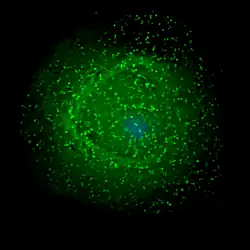

HI-Viren sammeln sich vor dem Verlassen der Immunzelle an der Membran.

HI-Virus, das sich aus einer Immunzelle herauslöst